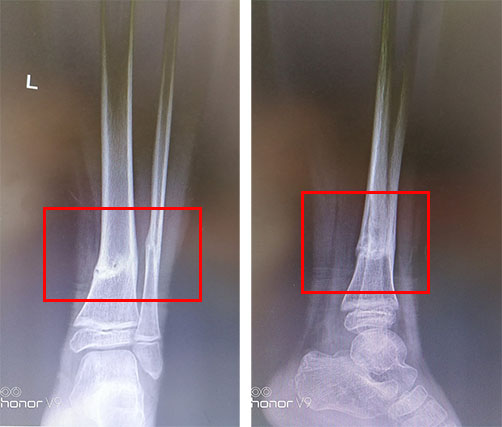

患儿,男,7岁,跌倒致左小腿肿痛畸形,即往当地医院就诊,予手法复位,石膏固定,现为伤后13天,来我院就诊,摄x线如下: